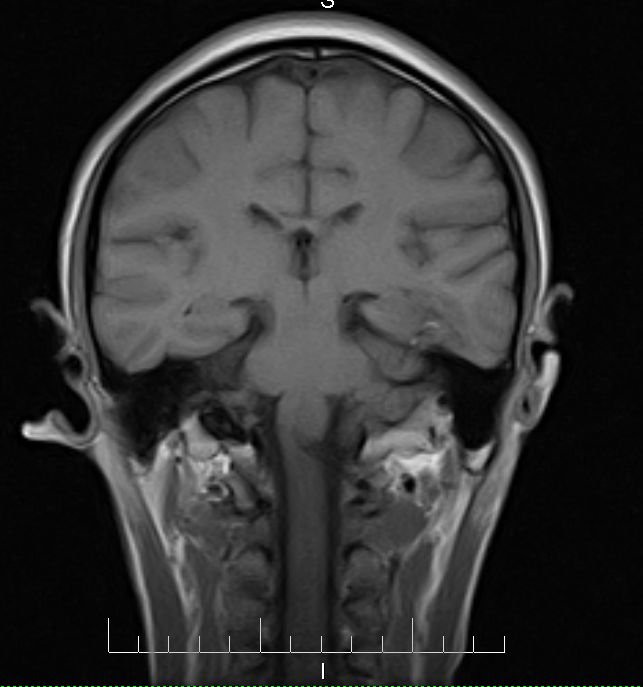

标题: MRI2379:30岁,男,癫痫10年,请各位看一下;CT示:左颞叶钙 [打印本页]

标题: MRI2379:30岁,男,癫痫10年,请各位看一下;CT示:左颞叶钙

左颞叶区见不规则点状混杂信号影

支持2楼 左颞叶区见不规则点状混杂信号影,考虑动静脉畸形。

考虑左侧颞叶脑血管畸形(avm)。----t1低等高混杂信号,t2等高信号周边较多流空血管影[冠状位明显],mra左侧大脑中动脉受压,远侧聚集.